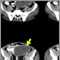

Una tomografía computarizada del abdomen generalmente revela un absceso intraabdominal. Después de realizar la tomografía, se puede colocar una aguja a través de la piel dentro de la cavidad del absceso para confirmar su diagnóstico y tratarlo.